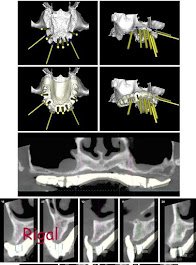

Combinamos un ambiente clásico, a veces hasta rústico, con protocolos, equipamiento y tecnología de última generación.

Para poder dar el mejor servicio hay que contar con la última tecnología, e instalaciones que garanticen nuestros tratamientos así como el bienestar del paciente.